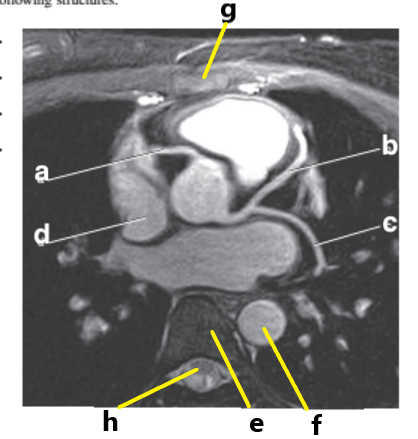

What is letter a ?

Ascending aorta

Aortic Arch

What is letter d ?

Right ventricle

What is letter g ?

Right atrium

What is letter b ?

Left ventricle

Pulmonary trunk

What is letter h ?

Descending aorta

Left anterior descending artery